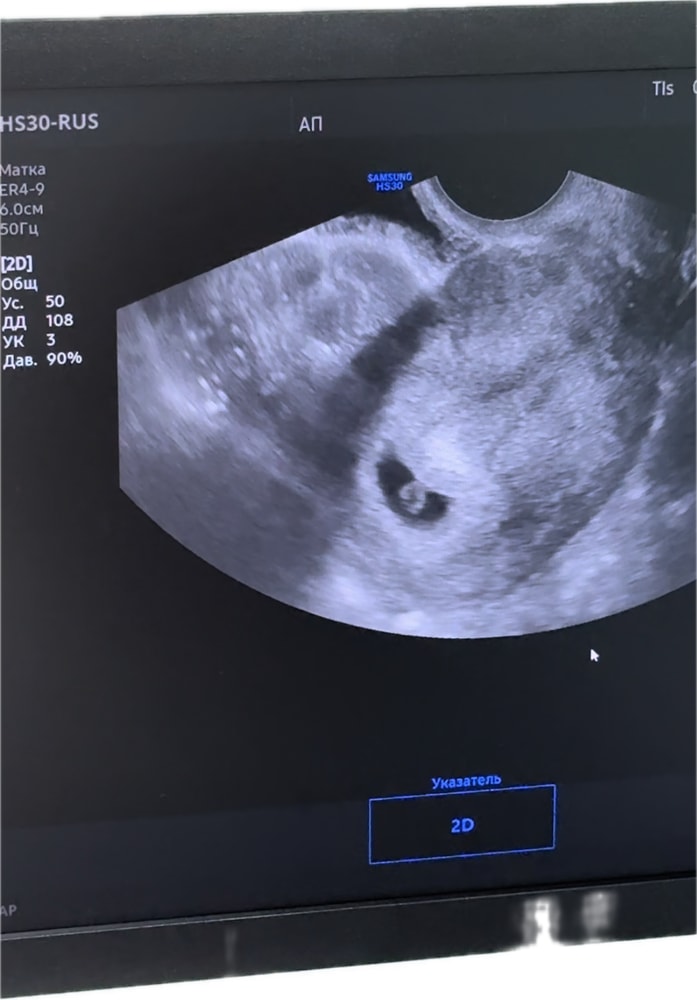

12.07.2025 сходили с мужем на первое узи, маточная беременность подтвердилась . Увидели нашу точечку и сердечко💗🥹